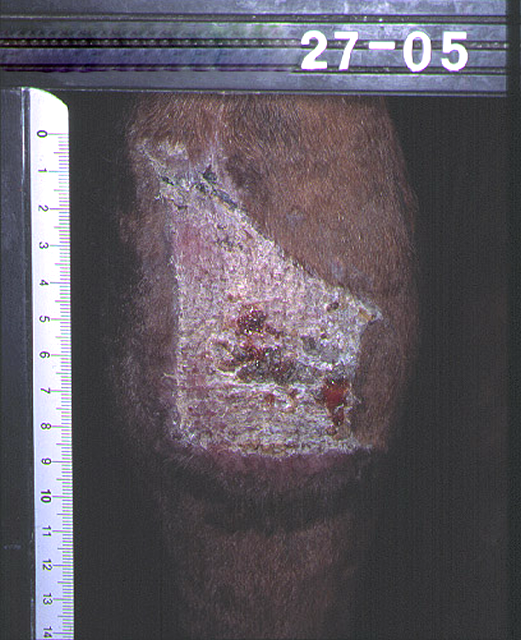

Een voorbeeld van een grote wond op de voorzijde van de sprong. De wond wordt onder het verband behandeld, en gaat slechts langzaam vooruit. Op 21 april wordt de voorbehandeling gestart voor huidtransplantatie en op 27 april wordt onder algehele narcose de huidtransplantatie uitgevoerd. Een maand later, op 27 mei, is de wond vrijwel geheel genezen. Het litteken is mooi rustig, vlak en soepel. Haargroei begint na ongeveer 6 weken. Hetzelfde paard ruim een jaar later: de sprong is mooi dun en het litteken behaard. Het paard draait dan al geruime tijd weer volledig mee in de sport.